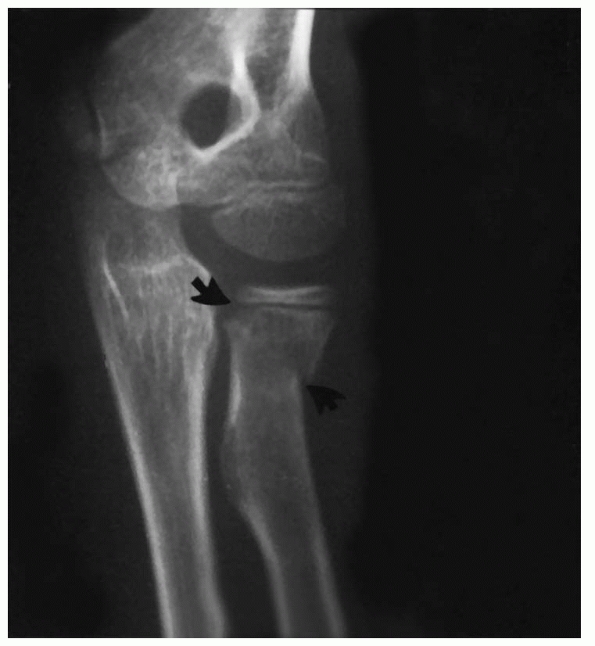

the elbow. The result may be a greenstick fracture of the ulna with an

associated fracture of the radial neck or avulsion of the medial

epicondylar apophysis (Fig. 11-45). If the fracture involves the radial neck, Bado35 classified it as an equivalent of the type I Monteggia lesion.

FIGURE 11-44 A. Anteroposterior view of a linear greenstick fracture line (arrow) in the medial aspect of the olecranon. B. Lateral view showing the posterior location of the fracture line (arrow).

|